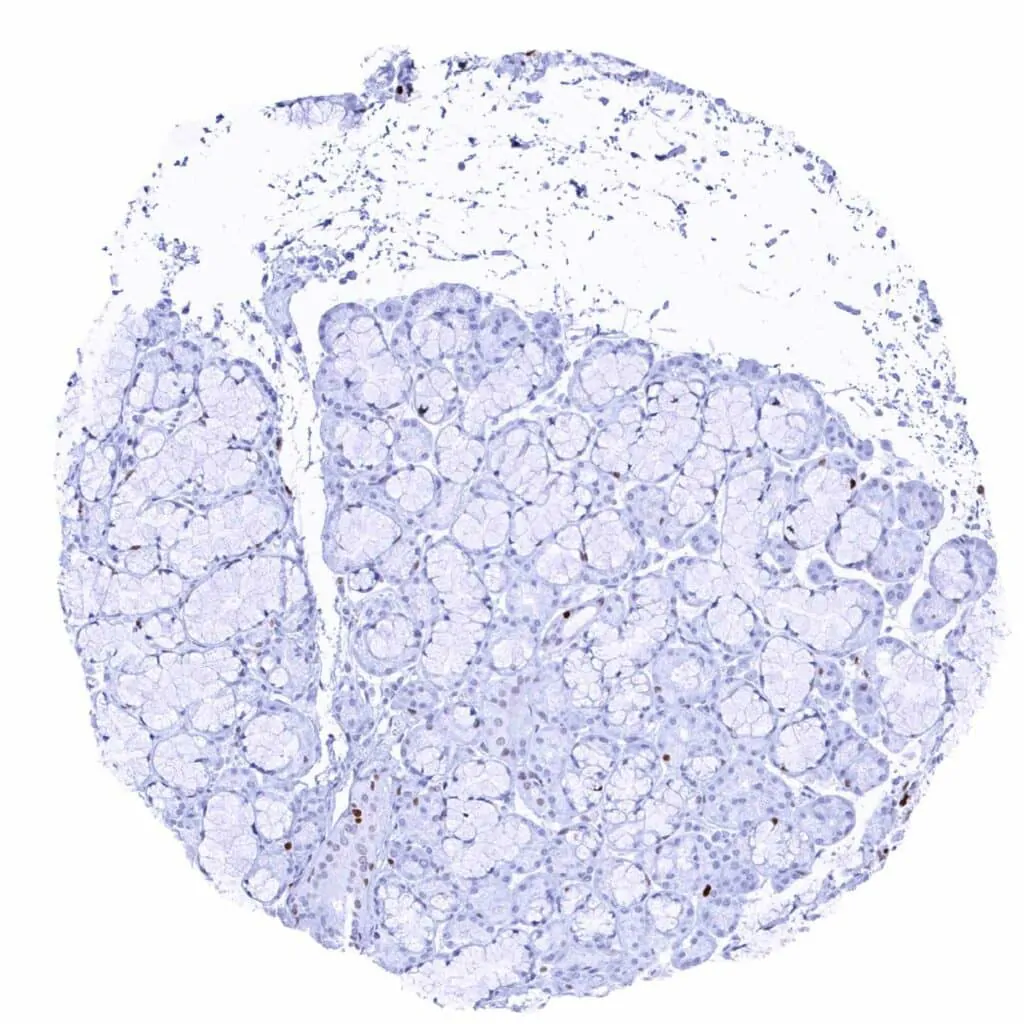

Prostate – MCM2 staining is more common in basal than in acinar epithelial cells